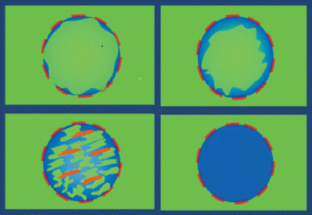

The aim of this study was to determine the accuracy of elastosonography in the differential diagnosis of thyroid nodules using a qualitative [evaluation of the stiffness score (SS)] and quantitative assessment [evaluation of the strain ratio (SR)].

Forty-four nodules were malignant (TIR ≥ 3) and 324 benign on cytological analysis. Considering a cut-off of SS > 2, we had 91 % sensitivity, 68 % specificity, 27 % PPV and 98 % NPV. Considering a cut-off of SR ≥ 3.28, we had 81.8 % sensitivity, 82.7 % specificity, 39.1 % PPV and 97.1 % NPV.

The SR calculation did not provide additional data to the SS, which remains the elastosonography benchmark. It will be necessary to validate these preliminary data by larger prospective randomised trials.